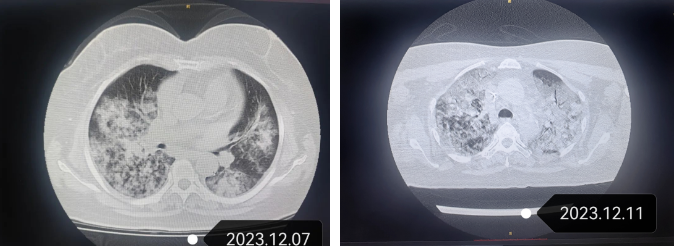

急诊科接诊后考虑病情较重,将李阿姨收入呼吸内科住院治疗。急查胸部CT提示,李阿姨双肺出现了“白肺”,即有重症肺炎,病情危急,立即被转到重症医学科(ICU)抢救。

▲CT显示,李阿姨双肺肺炎严重

12月11日复查CT影像提示,李阿姨双肺肺水肿,紧接着细菌基因检测结果显示,有偏肺病毒、疱疹病毒及真菌感染。

治疗5天后,李阿姨的血气分析氧分压达到187mmHg,氧浓度及流量一减再减,血氧饱和度一直维持在98%以上,成功由高频氧疗转变为低流量吸氧。12月15日,李阿姨复查胸部CT提示,肺炎较前明显好转。